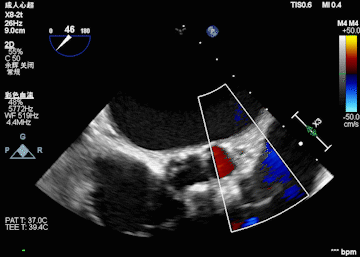

心脏超声

峰值流速:4.3M/s; 最高跨瓣压差:73mmHg; 平均跨瓣压差:43mmHg; 左室射血分数EF值:0.59; 左室舒张末期内径(LVD):5.3 cm。

主动脉瓣评估:三叶瓣,不均匀钙化,右无窦钙化交界处钙化严重,左冠瓣无明显钙化,瓣叶较厚,右无钙化明显。主动脉重度狭窄并中度关闭不全,二尖瓣轻中度狭窄,左房扩大,同时二尖瓣三尖瓣都伴有返流。

术前超声影像

术中球扩后超声影像

术后超声影像